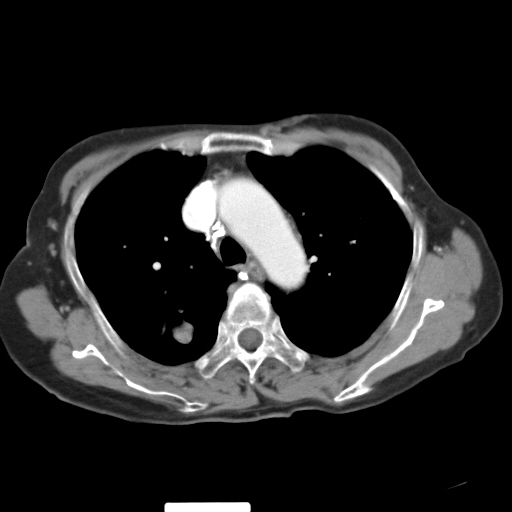

以下是引用hhcckk在2007-3-2 14:51:00的发言:[br]考虑结核球可能性大,依据[br]1病灶在下叶背段,结核的好发部位[br]2病灶内有大量的钙化,纵隔内有大量的淋巴结钙化[br]3重要的是半年前与现在相比无变化,假如是肿瘤的话不会这么‘善良’[br]4病灶周围卫星灶不明显,病灶有毛刺,胸膜凹陷,肿瘤不能完全排除,有条件的话最好做个活检

以下是引用liuyue在2007-3-2 17:15:00的发言:[br]1位置:右上叶后段[br]2性质:大分叶、粗长毛刺、条状斑片状钙化、纵隔多发淋巴结钙化,无强化,故考虑:肺结核灶(陈旧)